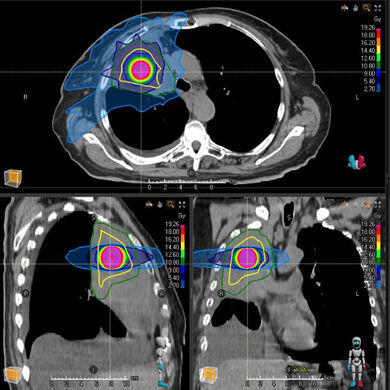

Abbildung: Simulation von räumlich fraktionierten Radiotherapie-Techniken.

Links: Lattice.

Rechts: Zentraler Tumor-Boost, aufgrund der technischen Analogie von uns auch als partielle SBRT (PARS) bezeichnet.